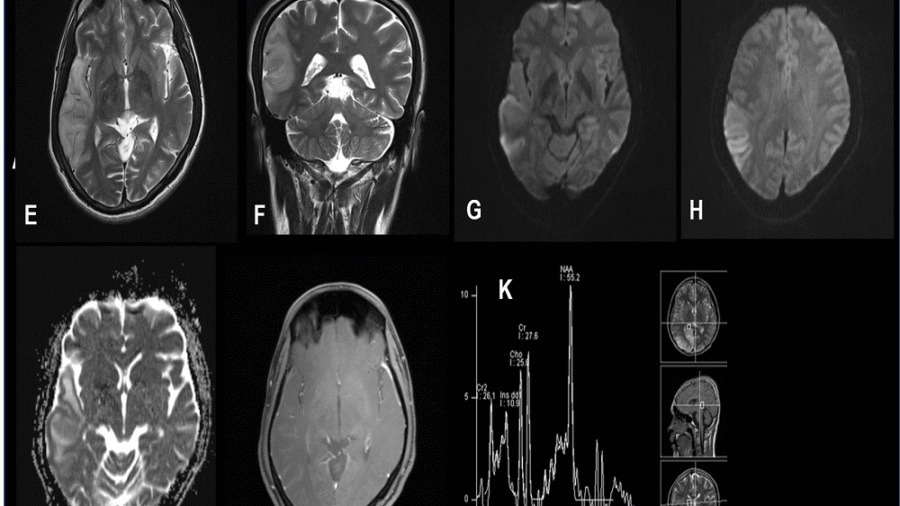

A 36 year old hypertensive male presented with gradually progressive weakness of bilateral upper and lower limb weakness since 1-2 months.